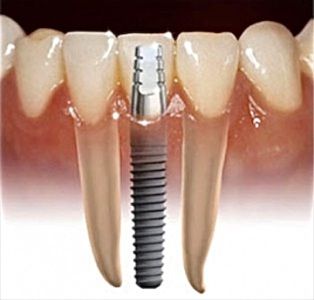

Фото. Имплантат, абатмент, коронка.